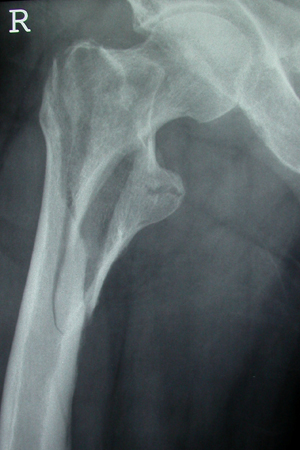

Con los tipos de fractura intracapsular, la ruptura de la corteza así como también de las líneas trabeculares primarias de tensión y compresión sugieren el desplazamiento de la fractura. El aumento de la angulación en varo o valgo en la imagen AP o el aumento en versión anterior o posterior observado en la radiografía lateral también sugieren desplazamiento y pueden compararse con la otra cadera intacta.

Con los tipos de fractura extracapsulares, la estabilidad de las fracturas desplazadas generalmente tiene en cuenta el grado de conminución y, más específicamente, la conminución de la corteza medial. Los tipos de fracturas intertrocantéricas simples de 2 fragmentos sin conminución del calcar medial (corteza) generalmente se consideran estables. Las fracturas intertrocantéricas de 3 y 4 fragmentos con ruptura de la corteza posteromedial o la fractura con oblicuidad invertida se consideran inestables.[3][51][Figure caption and citation for the preceding image starts]: Radiografía anteroposterior inicial que muestra una fractura intracapsular de la cadera izquierda desplazadaDe la colección de Bradley A. Petrisor, MSc, MD, FRCSC y de Mohit Bhandari, MD, MSc, FRCSC [Citation ends].